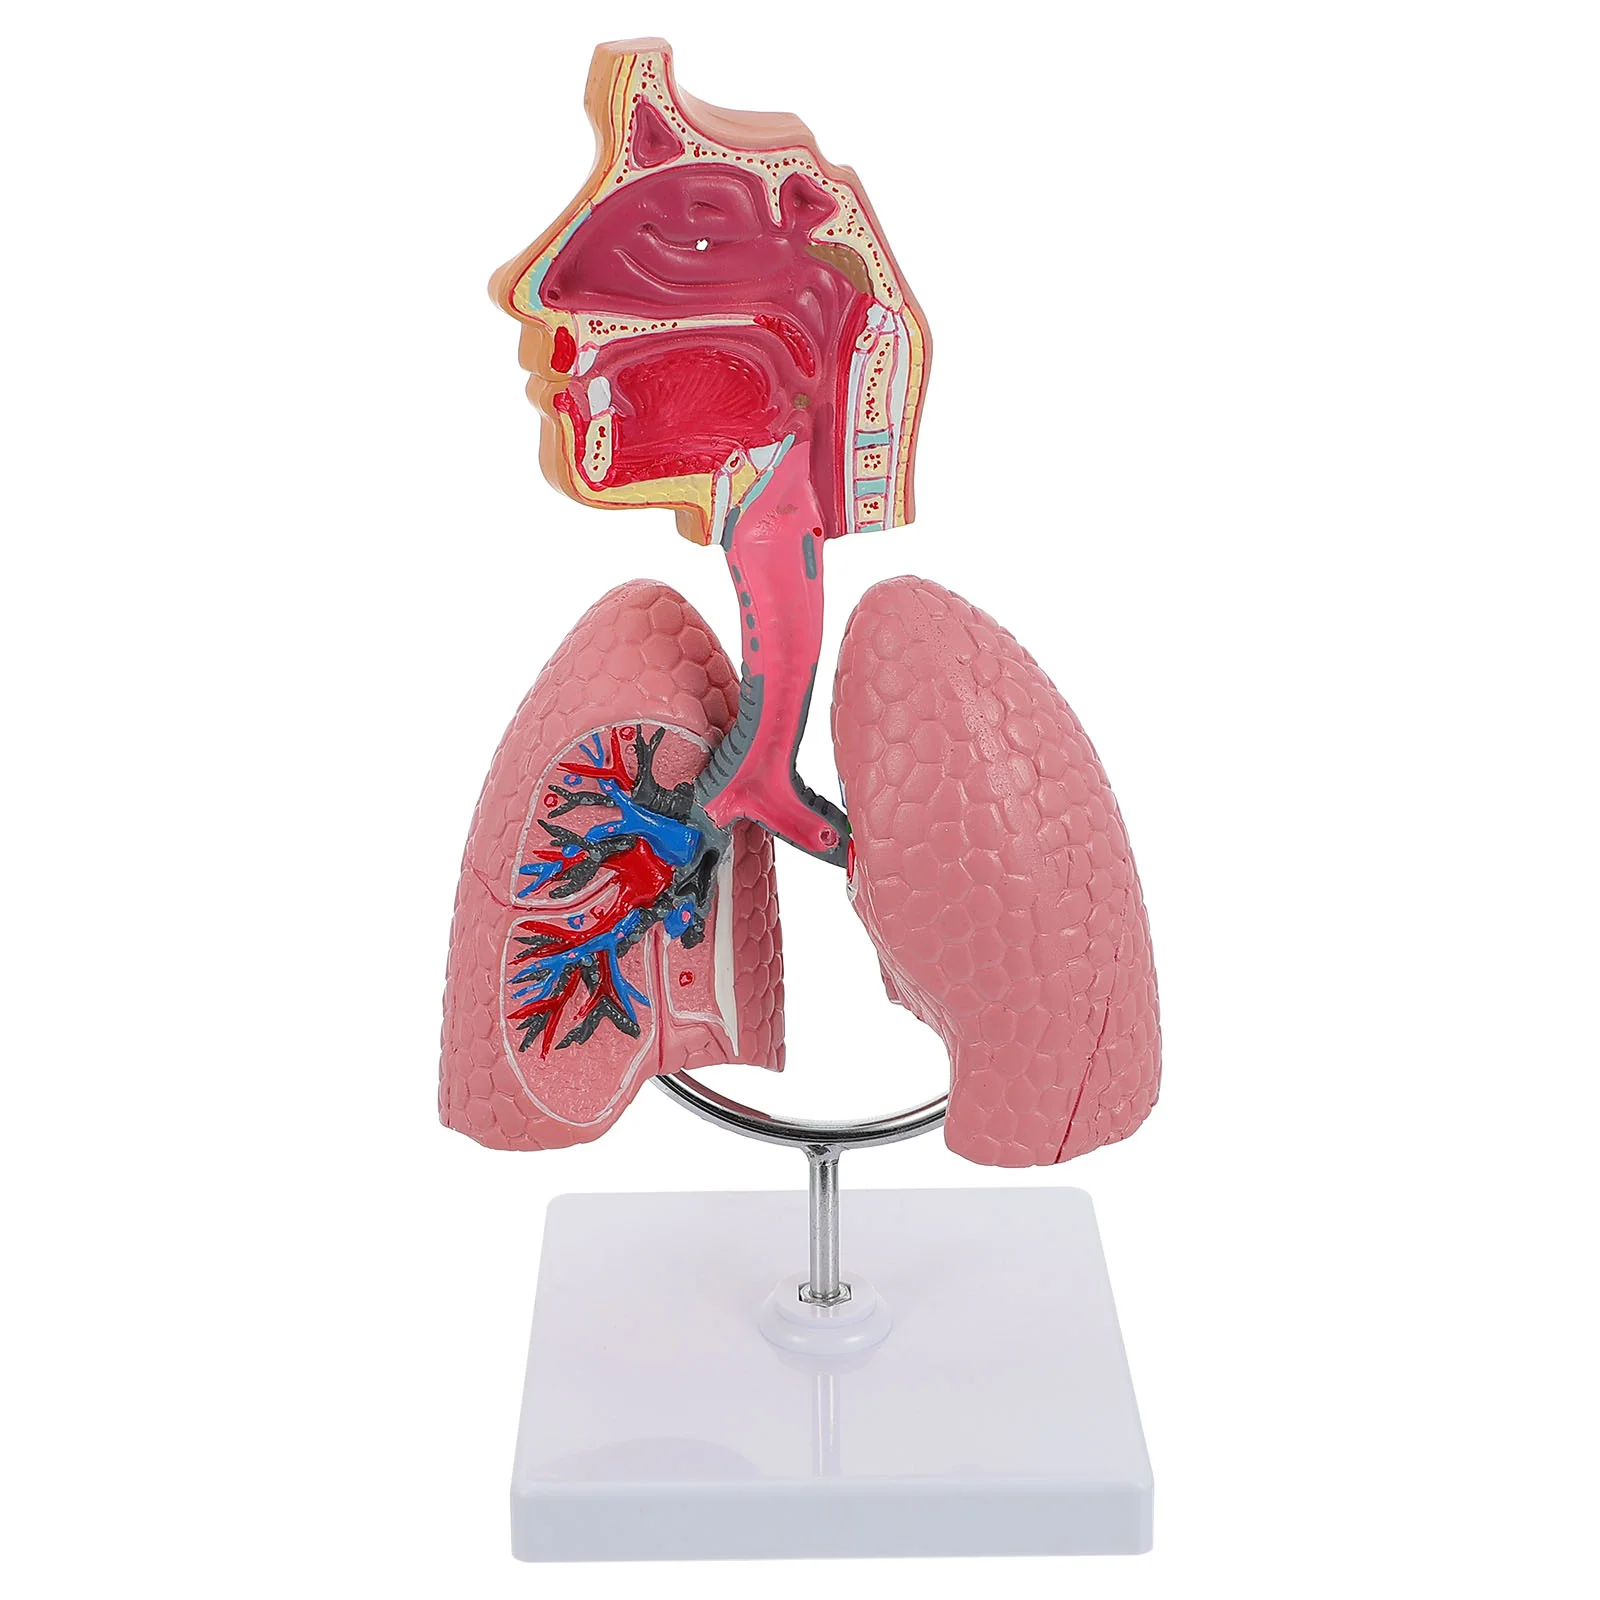

Model Lung Respiratory Teaching System Human Display Tool Anatomy School Lungs Anatomical Heart Educational Nasal Toy Nursing

sku: 1005005188844360

ACCORDING TO OUR RECORDS THIS PRODUCT IS NOT AVAILABLE NOW

$36.74